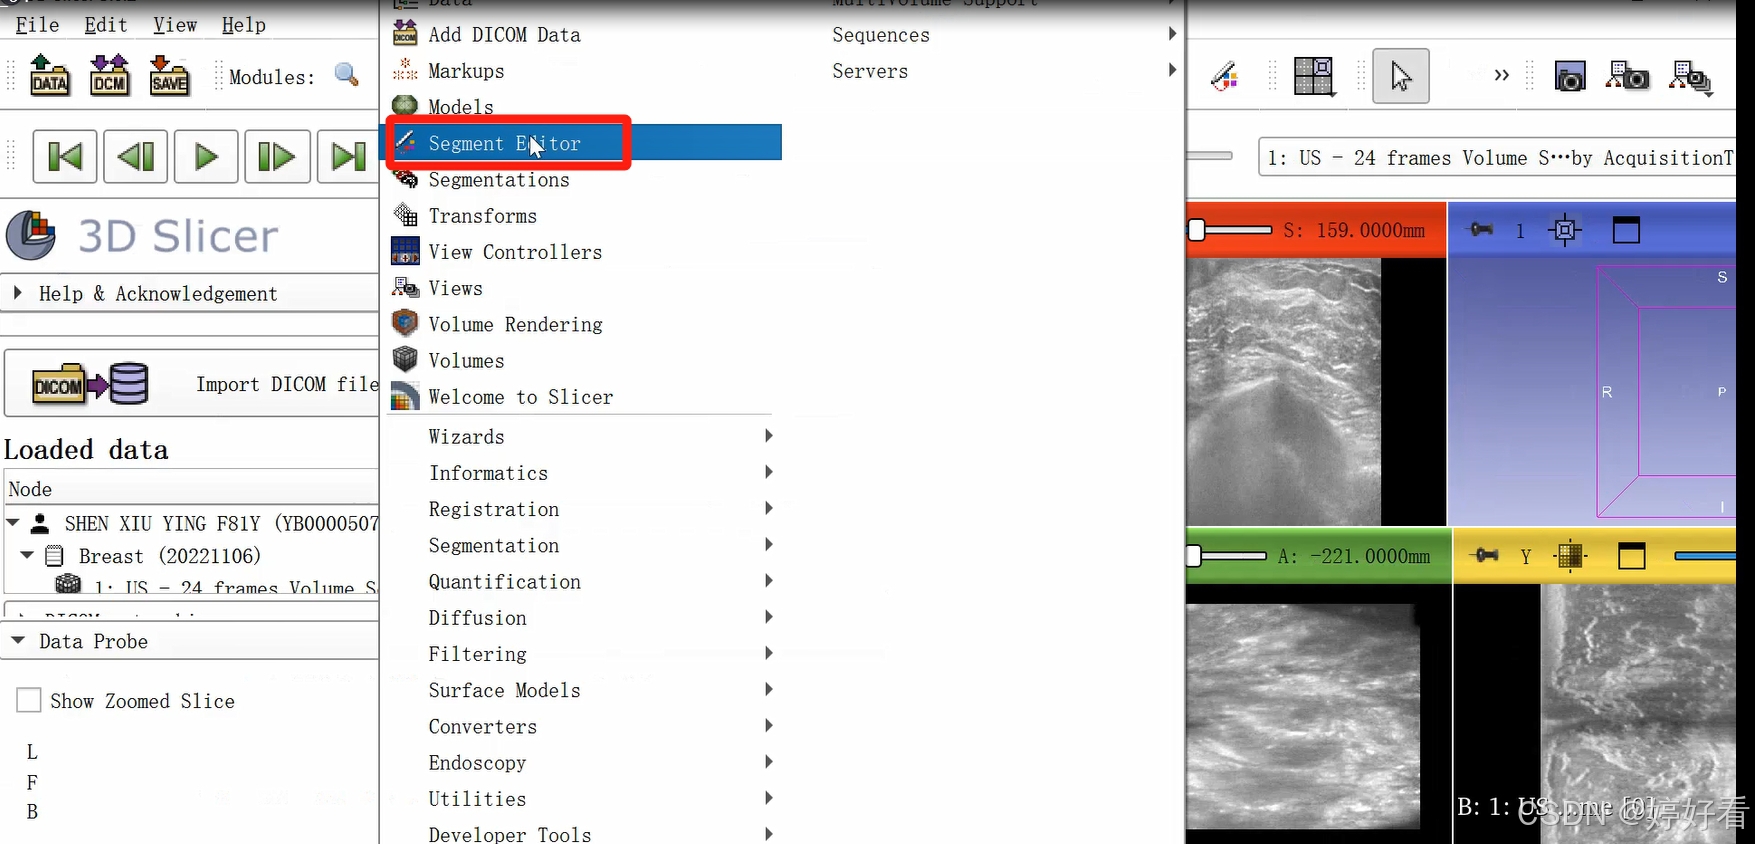

2、病灶分割

2.1 首先,点击以下图片中的下拉箭头,然后选择Segment editor。